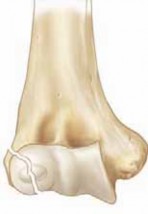

Chapter 33 Repair of Congenital Pseudarthrosis of the Tibia With the Williams Rod Perry L. Schoenecker and Ma…